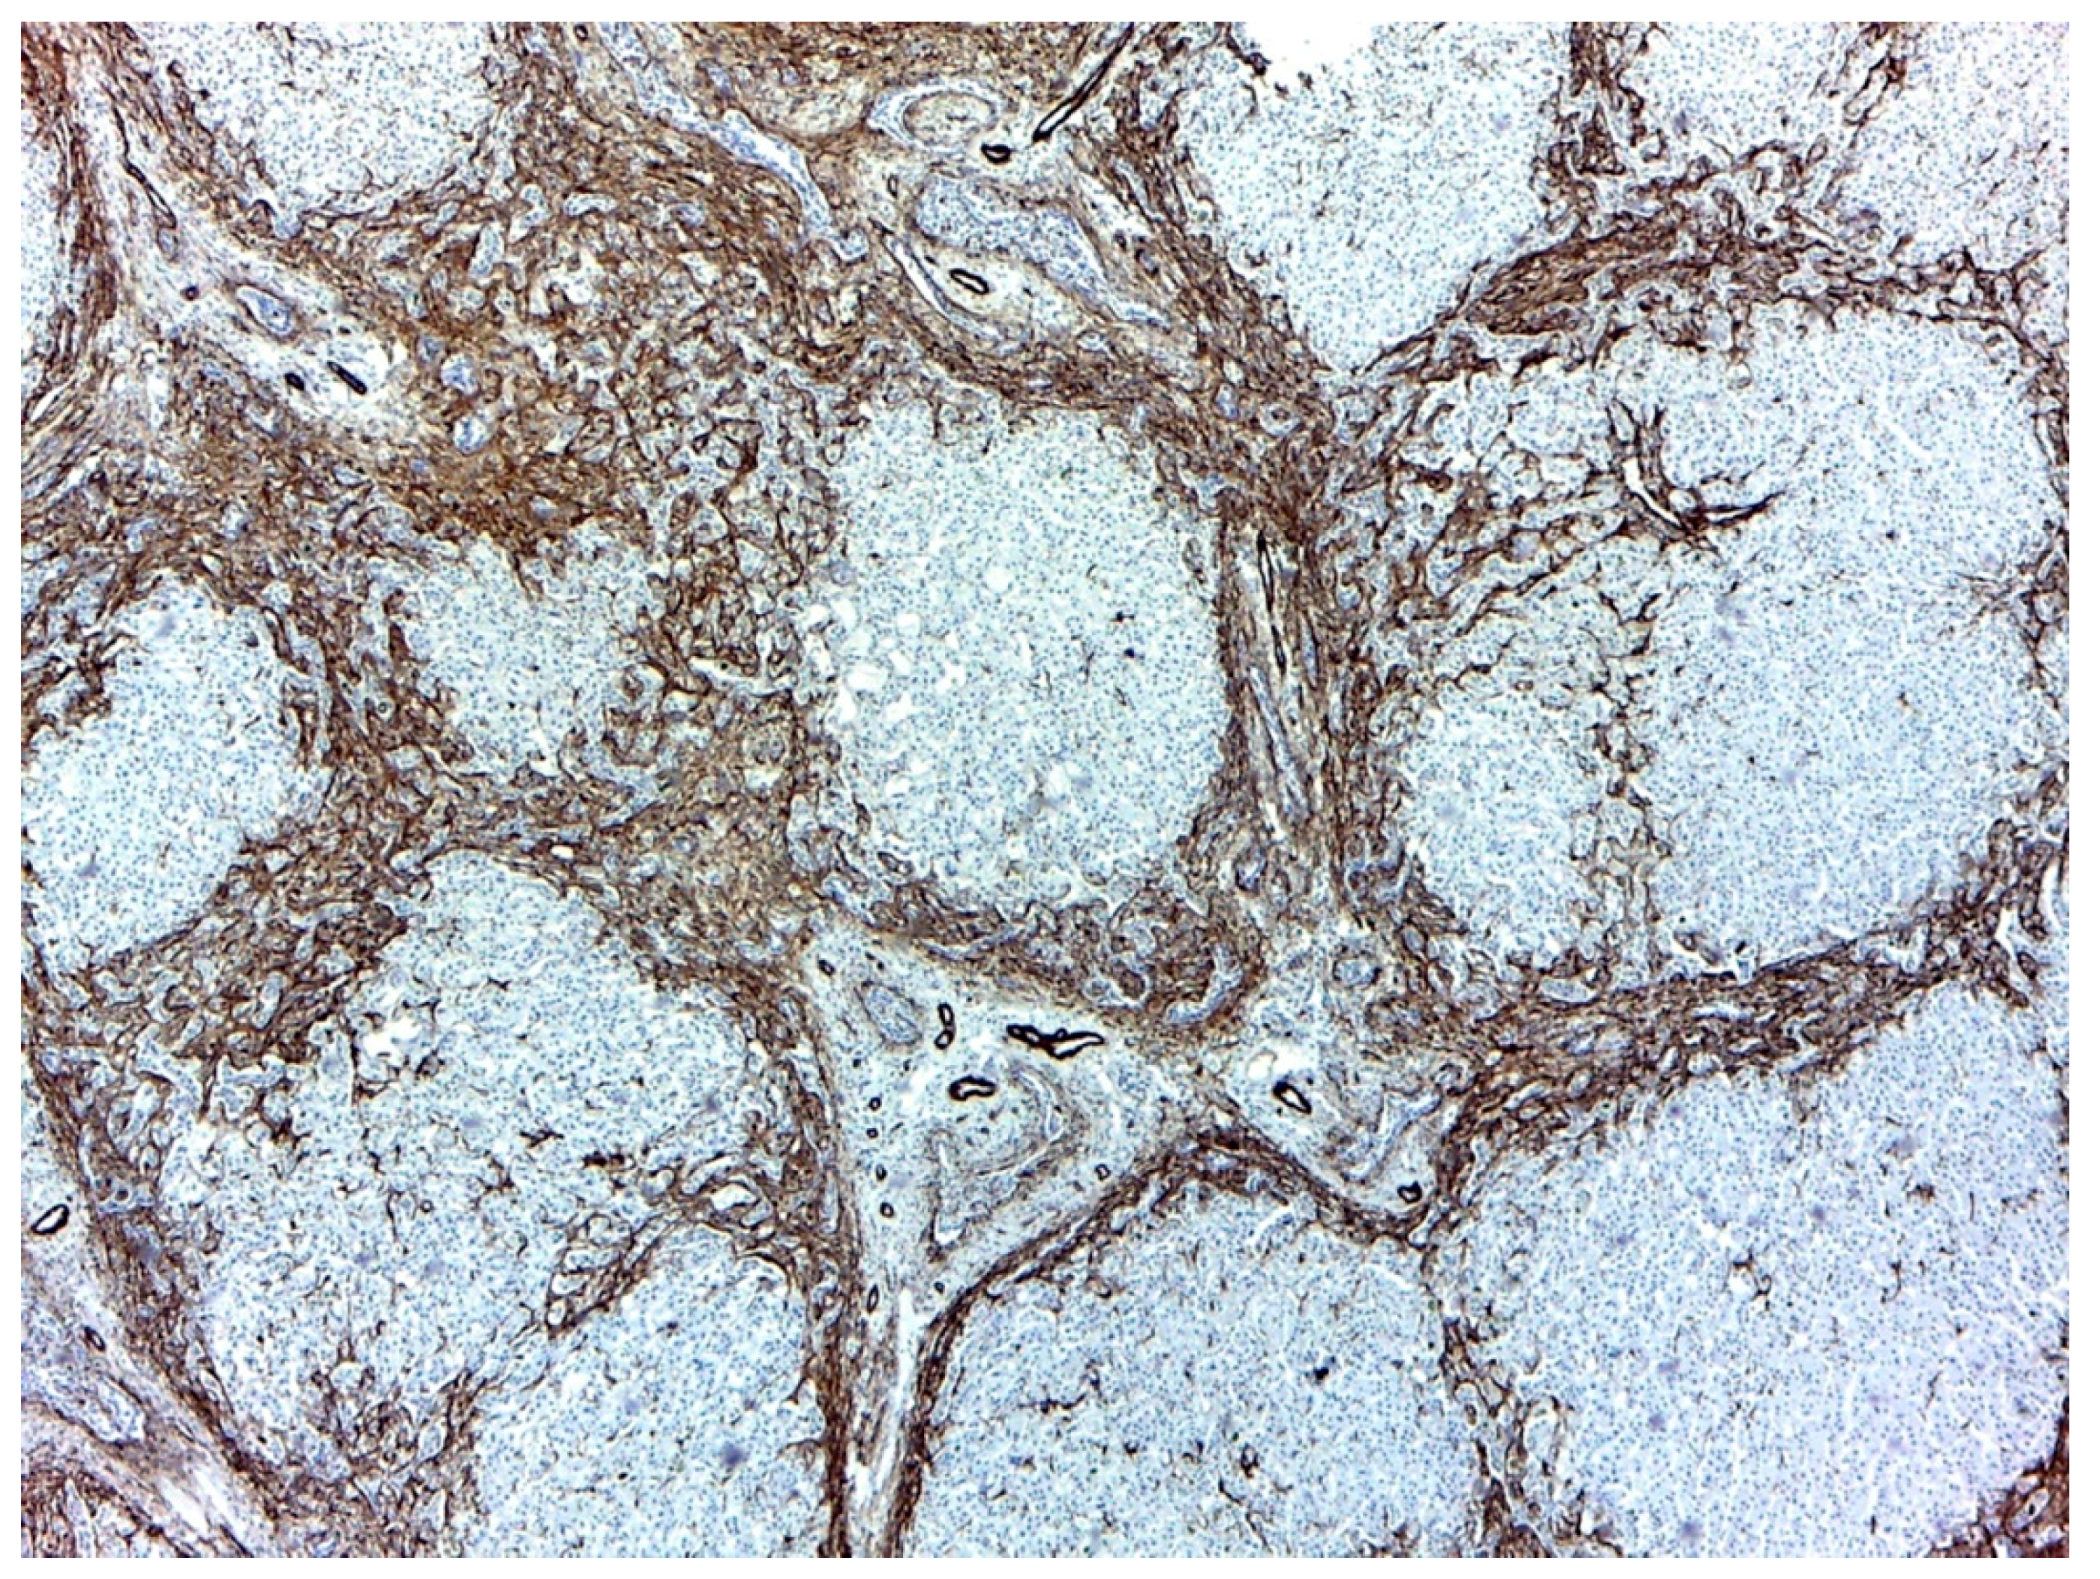

The analysis of the portal fibrotic tissue excised during surgery identified porta hepatis with rare bile ducts of medium caliber, with fibrous bridges. The fibrous septa presented in the central area irregular, collapsed bile ducts, with pan CK positive epithelium and in the periphery, ductular proliferation, similar to the embryonic ductal plate (Figure 1).

Figure 1.

Hepatic biopsy: (a). Bile ductular proliferation (CK7 (cytokeratin), 20×, 100 µm); (b). Liver nodules with no centrolobular vein, with intracellular and canalicular cholestasis (HE (hematoxylin eosin), 100×); (c). Ductal plate malformation (TM (trichrome masson), 10×, 200 µm).

The main histological changes identified in the hepatic parenchyma were hepatic lobules with irregular nodular organization, thick porto-portal fibrous bridges, and neutrophilic and lymphocytic inflammatory infiltrate. Moreover, regenerative nodules were identified, with no centro-lobular veins, surrounded by bridging fibrosis. Marked ductular proliferation was noticed peripherally, with a plexiform distribution in the central area of the bridges. Marked cholestasis, with ductal bile plugs both in the periphery and in the interhepatocyte ducts was a characteristic aspect.